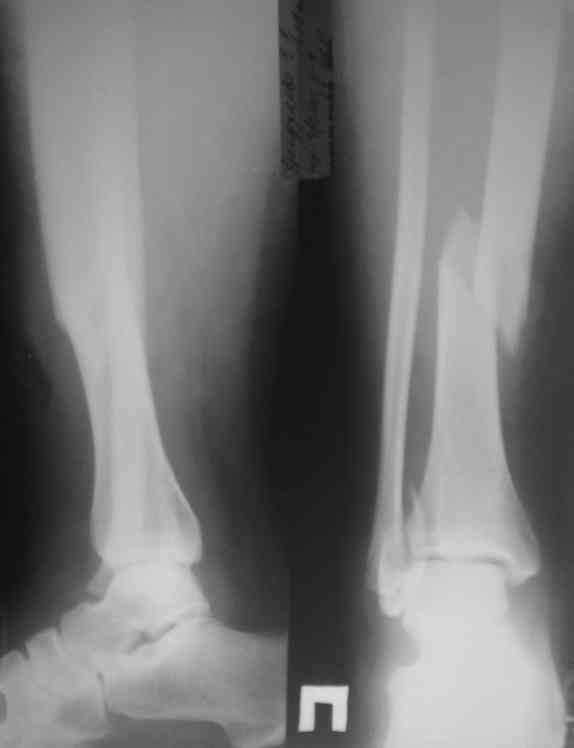

Представляю рентгенограмму перелома обеих костей голени, где определяется разрыв дистального межберцового синдесмоза.

С уважением, Юрий